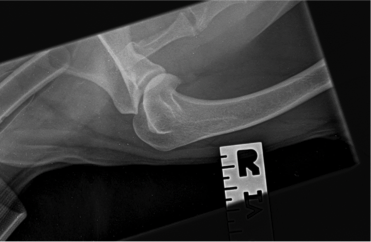

- With deterioration and lack of resolution of Charlie’s discomfort he was referred to Weighbridge Referral Centre for radiographs and evaluation of his right forelimb and cervical spine. A small osteophyte was found along the caudal border of the humeral head and there was evidence of remodeling of the medial coronoid process which could be indicative of a degree of elbow dysplasia; however, these findings did not necessarily explain the degree of pain that Charlie has been experiencing clinically. The owner reported that this week prior to our evaluation had been particularly painful for Charlie. He is currently on Metacam, but the owner does not believe that it is helping as much as it did when Charlie was initially placed on the medication.

- Radiographs: